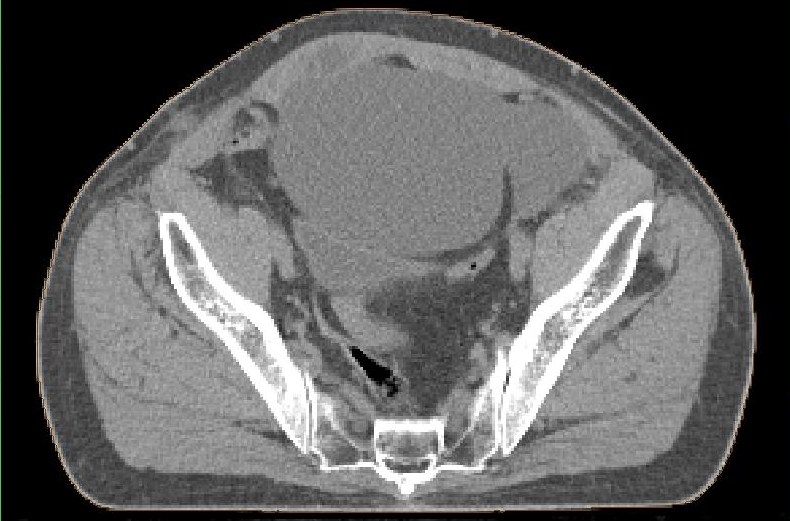

postoperative Lymphozele

Große Lymphozelen nach laparoskopischer pelviner Lymphonodektomie.